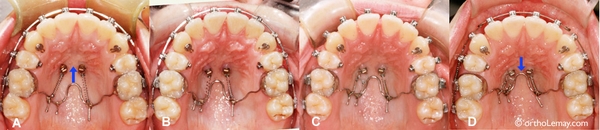

Xử trí răng mọc ngầm

TheoTS.BS.Nguyễn Phú Thắng : Răng ngầm là một hay nhiều răng nằm trong xương hàm trên hay xương...

Chỉnh nha với sự hỗ trợ của minivis

Tóm lại , Minivis rất cần thiết cho các Bác sỹ chỉnh nha , là khí cụ neo...

Cấy chuyển răng – kỹ thuật cao

Tại Việt Nam , Từ năm 2012 , TS.BSNT.Nguyễn Phú Thắng và học trò cũng áp dụng phương...